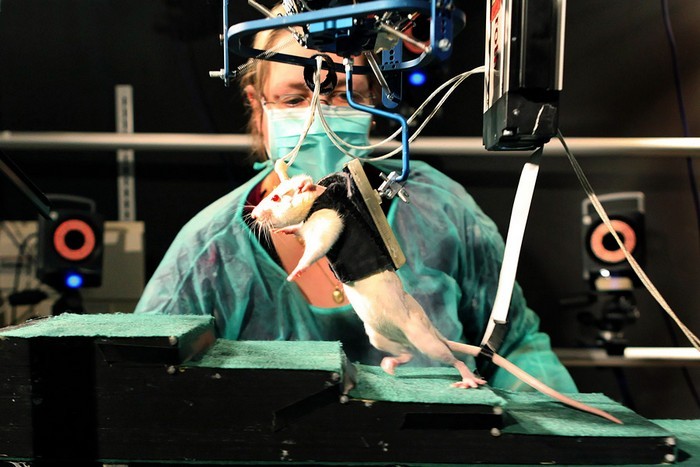

Биология. Парализованная крыса снова начала ходить

2014-й год принес надежду миллионам людей, которые навсегда прикованы к инвалидным коляскам. Ведь ученые заявили, что даже максимально поврежденный спинной мозг – это еще не окончательная гарантия, чтобы вы никогда больше не сможете ходить.

Парализованная крыса снова начала ходить

Поводом для оптимизма могут стать результаты исследований, в рамках которых швейцарские ученые сначала полностью перерезали посередине спинной мозг крысе, а потом снова научили ее ходить. Они вживили гибкие электроды в позвоночник грызуна чуть ниже линии разреза, а затем адаптировали параметры передаваемого таким образом электрического импульса к нервной системе животного.

Парализованная крыса снова начала ходить

В результате крыса смогла не только бегать, но даже преодолевать разные препятствия, в том числе, подниматься по лестнице. Ученые обещают начать подобные эксперименты на людях летом 2015 года.